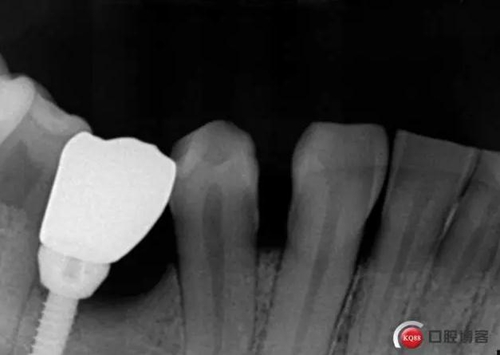

牙冠